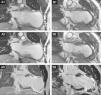

Transthoracic echocardiography (TTE) depicted a severely dilated LV with a large anteroapical aneurysm and severe LV dysfunction (Figure 2A1), which was also seen on the cardiac computed tomography scan (Figure 2A2). Mild mitral regurgitation was present. Due to the absence of tricuspid regurgitation, pulmonary artery systolic pressure could not be estimated.

(A1) Baseline transthoracic echocardiogram in 4-chamber view showing the large LV aneurysm and preserved basal segments; (A2) cardiac computed tomography (CT) scan before the procedure to assess the possibility of percutaneous treatment; (B1) intraoperative transesophageal echocardiogram showing normalization of ventricular shape and reduction of LV volume; (B2) cardiac CT scan post-procedure showing the anchor pairs and absence of contrast leakage between the excluded scar and the LV.

The procedure lasted 209 minutes (skin to skin). No complications occurred. TEE at the end of the procedure showed normalization of ventricular shape, significant reduction of LV volumes (>50%) and slightly improved EF (Figure 2B1). The patient was discharged home on the 7th day post-procedure. On discharge, no leakage between the excluded scar and the LV was observed (Figure 2B2).